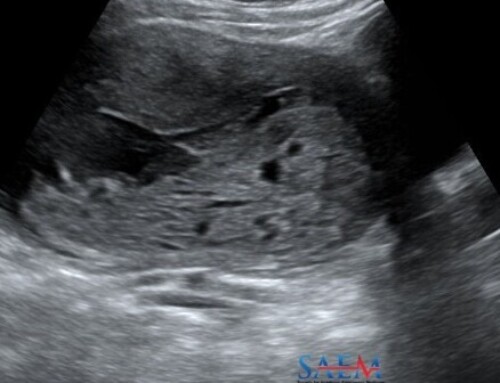

| ALiEM: Trick of the Trade: Linear transducer for POC US in IUP evaluation | Amy Phillips, MD and Mark Favot, MD | 6/4/17 | HM |

| CoreEM: Ectopic Pregnancy: Pitfalls in Diagnosis | Matt McCarty, MD | 6/7/17 | HM |